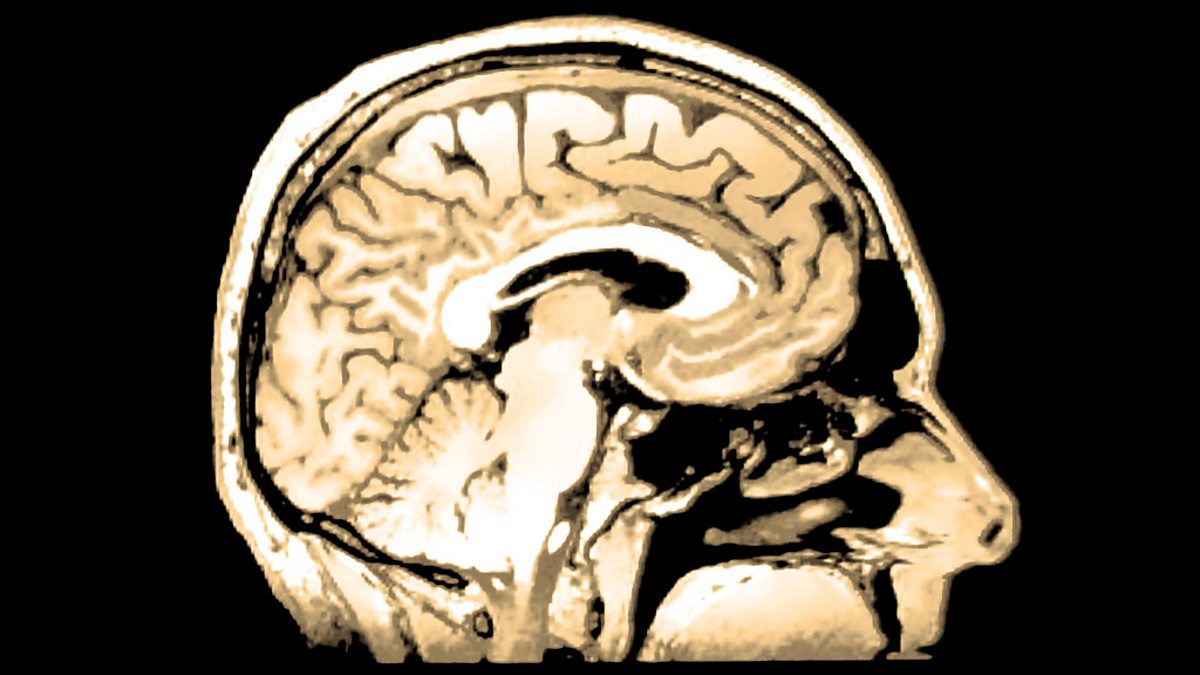

Permanent Present Tense by Suzanne Corkin is the fascinating story of the life and legacy of Henry Molaison. In 1953 Henry underwent an experimental brain operation to alleviate his debilitating epilepsy which had a devastating and unexpected side effect. Henry was unable to store or recall any new memories, no longer could he remember the faces of new people he met, the places he visited, the moments he lived through, and the myriad experiences of everyday life. Memories slipped from him after just thirty seconds. Following the medical procedure he became the subject of research into neuroscience and went on to transform the way the scientific community understand memory and how it functions. This book is both a biography of Henry (known in the media and the world of science as HM), and the development of neuroscience over the course of the fifty years from the date of Henry's operation to his death in 2008.